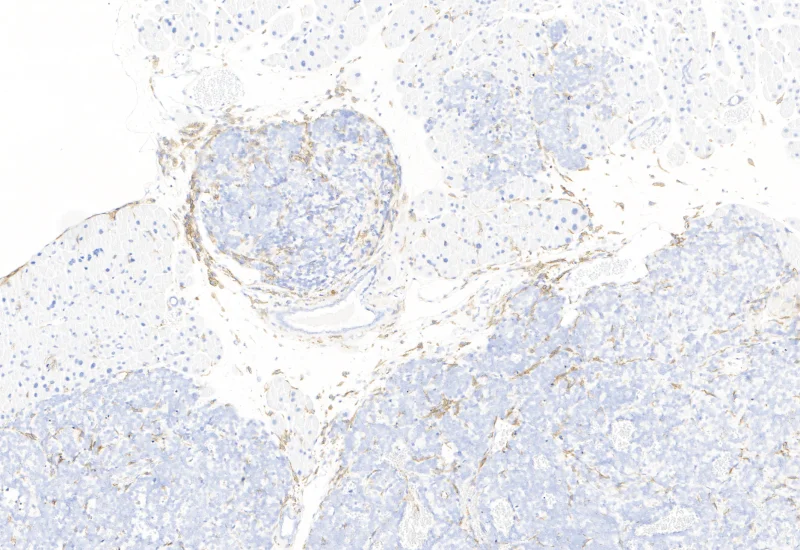

Original Image

The IHC Tumor-Macrophages APP provides tissue detection including separation into tumor tissue and healthy tissue. It detects macrophages based on a specific staining (e.g. CD68). The APP outputs the area of macrophages within tumor tissue and healthy tissue.

Image courtesy of Dr. Patrick Michl, Dr. Maren Egidi and Dr. Heidi Griesmann, Universitätsklinikum Halle (Saale)

Segment tissue into tumor and healthy areas, detect CD68+ macrophages, and quantify macrophage area within each tissue compartment.